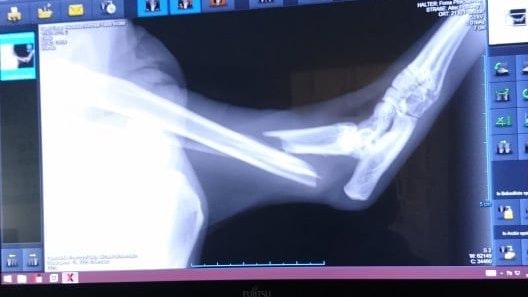

Der Kater wurde von der Besitzerin nicht versorgt.